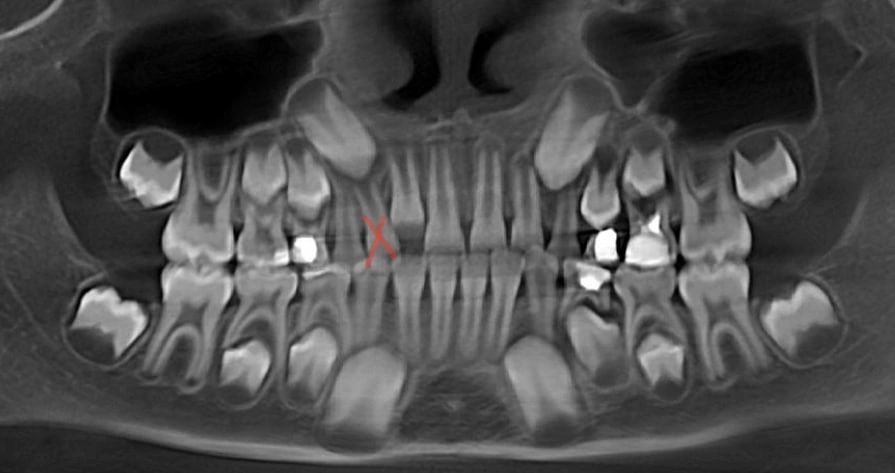

а это точно ваш снимок? или просто сделан давно? на снимке передние верхние зубы молочные, а на вашем фото верхние уже коренные стоят

Таша, снимок сделан 2 недели назад как и фото. Пару дней назад вот прислали на почту.

Вот они два одинаковых. И на том снимке пломбы как раз на тех, которые лечили

Но у нас в меня он видимо, у меня было клыков по три штуки. То есть сначала одни молочные, выпали рано. Полезли ещё, думали коренные а оказались молочные. Выдрали их, так лезли ещё уже коренные. С сыном делали 3д снимок. Эти два зуба полностью одинаковые, но один лишний. И если его не удалить, то новому который брат близнец некуда будет встать(

Анна, там реально лишний резец. И он вырос далеко от центрального резца, потому что ему мешал резец, который ещё в десне. В целом, у ребёнка узкая верхняя челюсть, у детей должны быть диастема и тремы (щели между резцами), это запас места для роста новых зубов. Скорее всего, сейчас лишний зуб выдернут, дождутся, когда вылезут все резцы и поставят расширяющую пластинку на верхнюю челюсть.